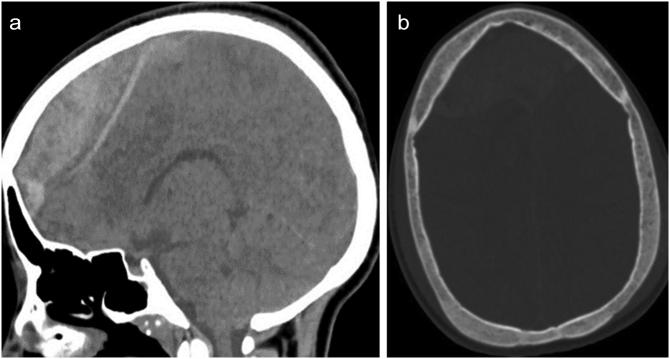

Massive spontaneous subdural hemorrhage mimicking dural venous thrombosis in a sickle cell adolescent, a rare case report.

We report a rare case of acute spontaneous subdural hemorrhage in an adolescent sickle cell patient of African descent.

我们报告了一例非洲裔青少年镰状细胞病患者急性自发性硬膜下出血的罕见病例。